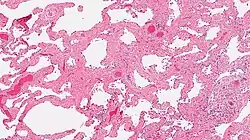

Smoking-related interstitial fibrosis (SRIF) is an abnormality in the lungs characterized by excessive collagen deposition within the walls of the air sacs (interstitial fibrosis). This abnormality can be seen with a microscope and diagnosed by pathologists. It is caused by cigarette smoking.[1][2]

The defining feature of smoking-related interstitial fibrosis is a distinctive/unique type of fibrosis characterized by "ropey" collagen bundles within the walls of the air sacs (alveoli), almost always in association with other smoking-related abnormalities such as pigmented macrophages and emphysema.[6]